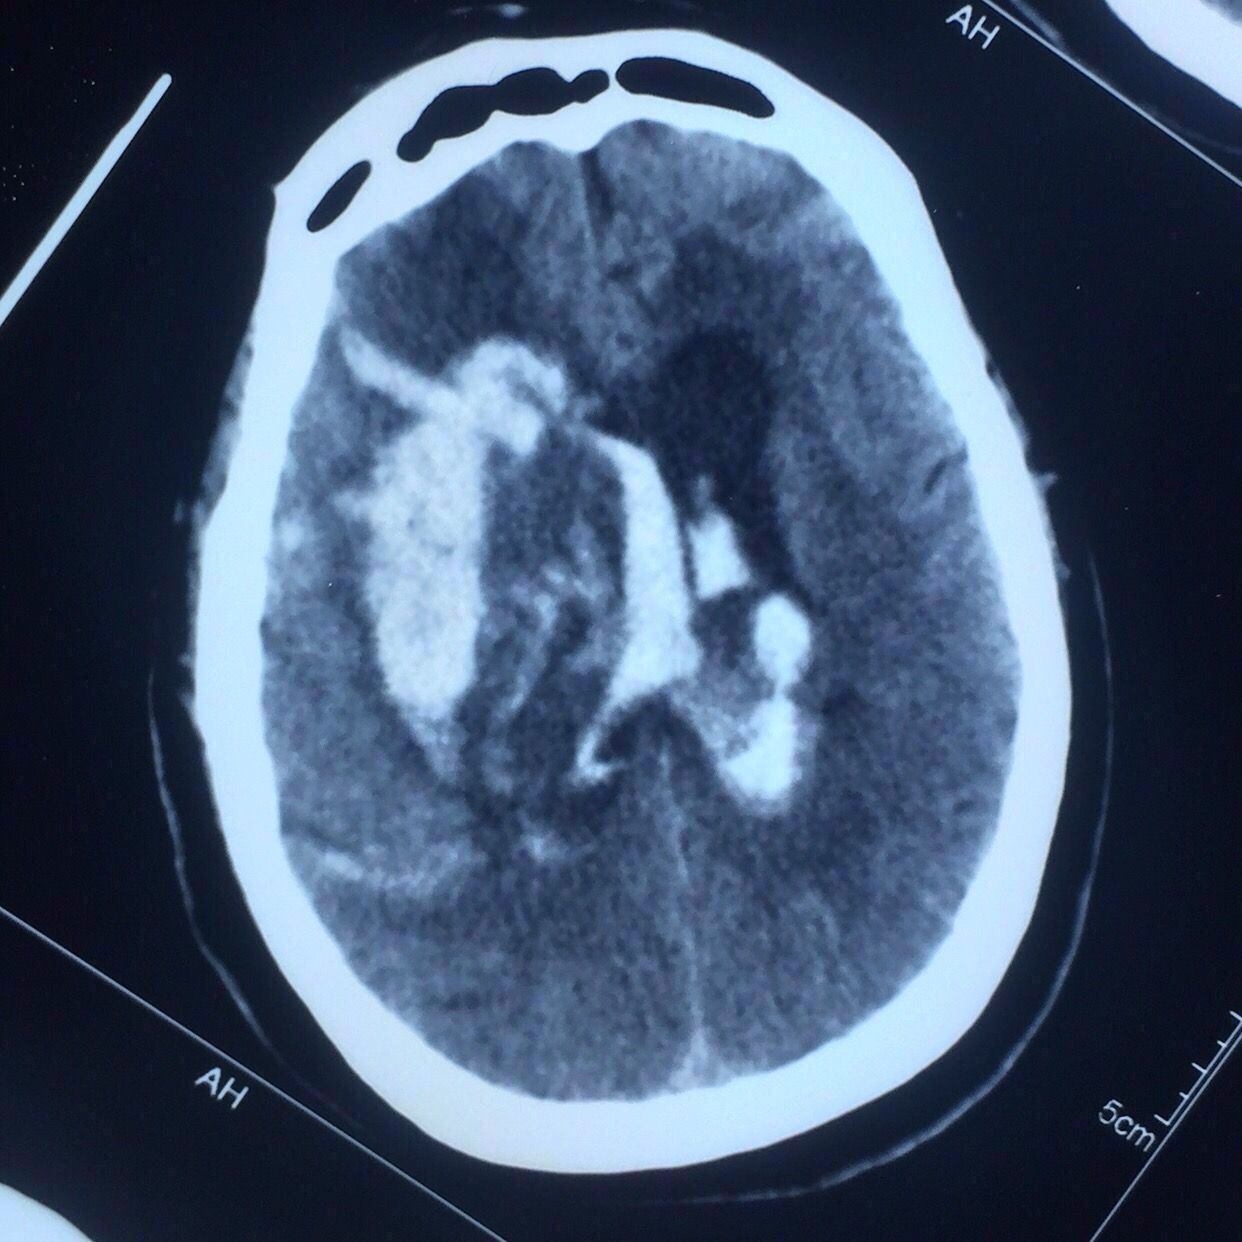

术后第7天复查,见上图,血肿引流比较充分。

患者仍昏迷状态,肺部感染较重,家属最终放弃气管切开手术放弃进一步治疗,出院回家。

总结:对基底节血肿来说,穿刺的位置并不拘泥于颞部或前额部,冠状缝前的额中回区域也是不错的选择,当然要根据具体的血肿形态而定。